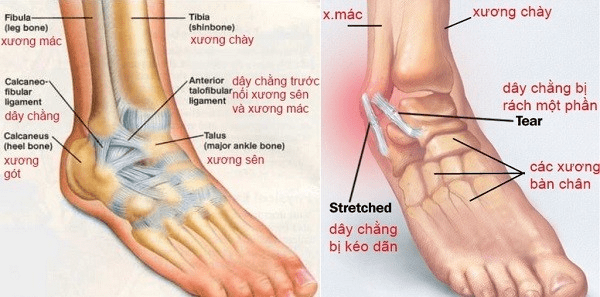

Gân Achilles là bộ phận nối cơ bắp chân với xương gót chân và tham gia vào hầu hết các hoạt động liên quan đến chân như đi lại, chạy nhảy. Do đó, khi gân Achilles phải hoạt động quá mức, đặc biệt là với những người thường xuyên hoạt động thể thao hoặc làm các công việc đặc thù, gân có thể bị tổn thương, dẫn đến viêm gân Achilles với các triệu chứng như khó di chuyển và sưng đau vùng gót chân.

Các vấn đề như yếu cơ, khớp cổ chân lỏng, vận động nhiều, thừa cân, béo phì… là những nguyên nhân hàng đầu gây tổn thương và viêm cơ gót chân. Bệnh gây cảm giác đau nhức, khó chịu cho người bệnh trong sinh hoạt thường ngày. Nếu không được phát hiện và điều trị sớm có thể dẫn đến viêm gót mạn tính, rách gân,..

Các tác động mạnh như té ngã, va chạm có thể gây tổn thương trực tiếp tới xương. Nếu không được xử lý sớm có thể dẫn đến viêm xương gót chân, nứt, gãy xương khiến người bệnh bị sưng nề, đau nhức, khó di chuyển…

Vận động với tần suất cao, té ngã, va đập mạnh… là những nguyên nhân hàng đầu gây tổn thương và viêm gót chân. Tùy vào mức độ chấn thương mà người bệnh có thể cảm thấy đau từng cơn, đau âm ỉ, bàn chân thiếu linh hoạt, khả năng vận động bị giới hạn…